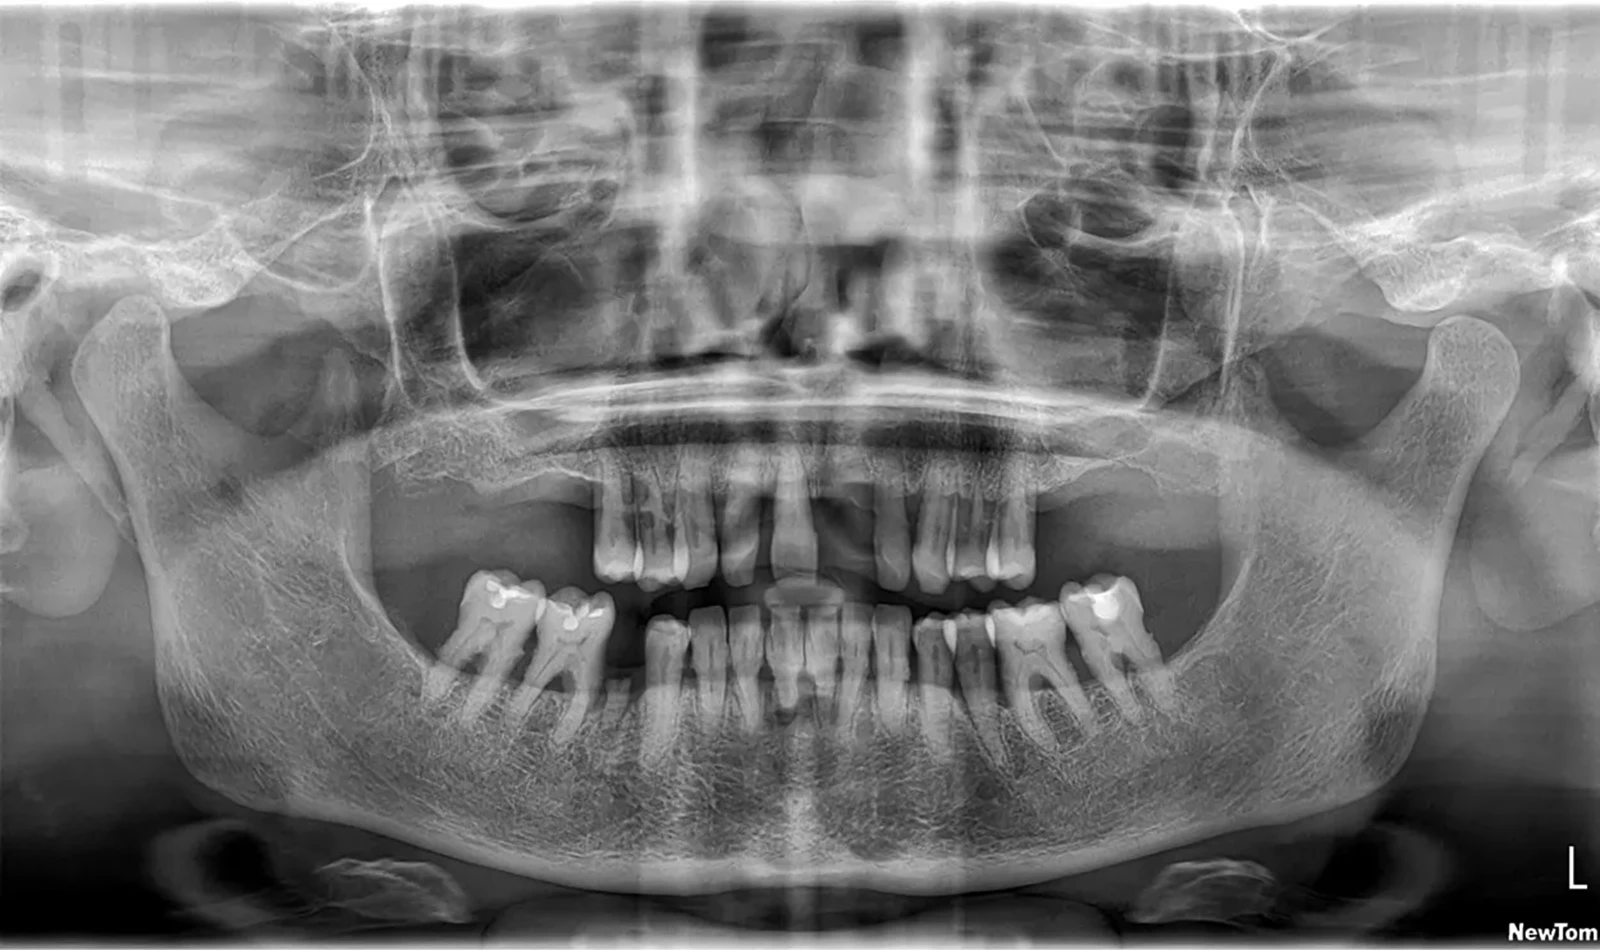

Paciente #1:

Paciente de 60 años, sufría porque sus dientes se movían y temía perderlos todos, pero gracias a la cirugía guiada y la técnica de carga inmediata, en un solo día Merche recuperó una sonrisa fija y natural. Volvió a comer, hablar y sonreír con mayor comodidad desde el primer momento.